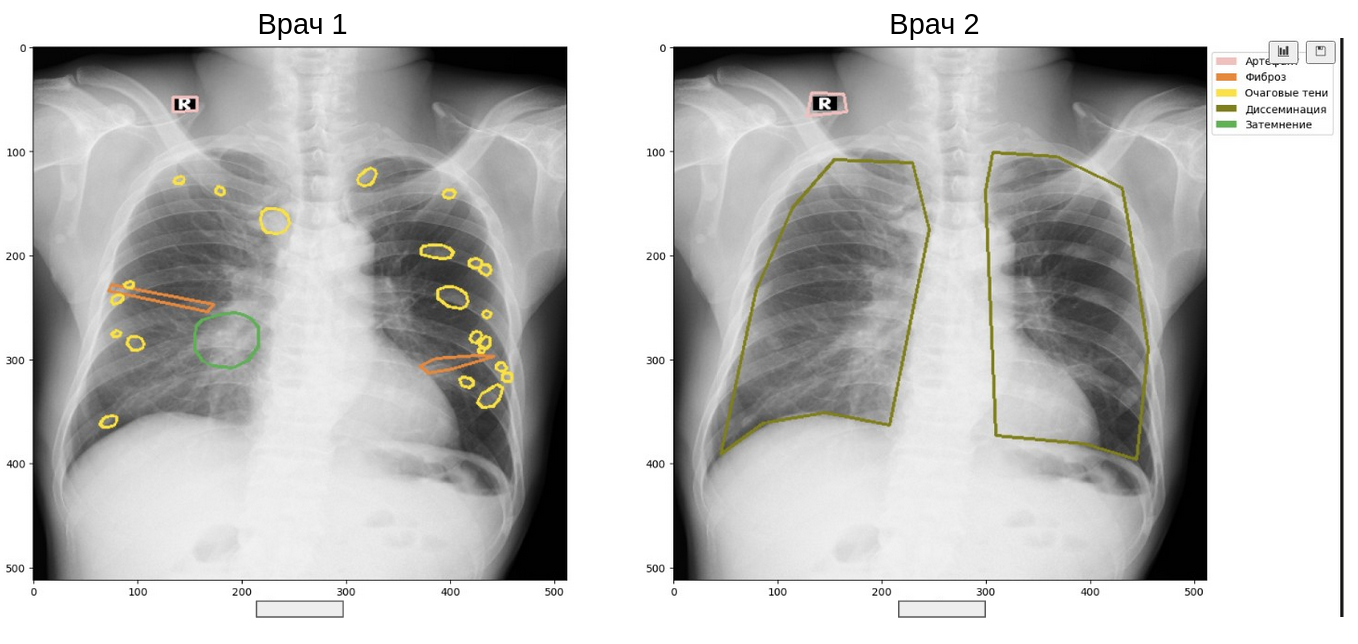

Если вы смотрели хоть одно моё выступление, то, наверняка, слышали нытьё про расхождения в разметке врачей. Например, такие:

Цветные кружочки в лёгких

Верифицированных данных (где диагноз подтверждён другим анализом или событием) в медицине немного, поэтому приходится жить с тем, что на одно исследование у нас обычно есть 2-5 вариантов разметки. Как считать метрики качества какой-нибудь модели детекции или сегментации в таком случае?